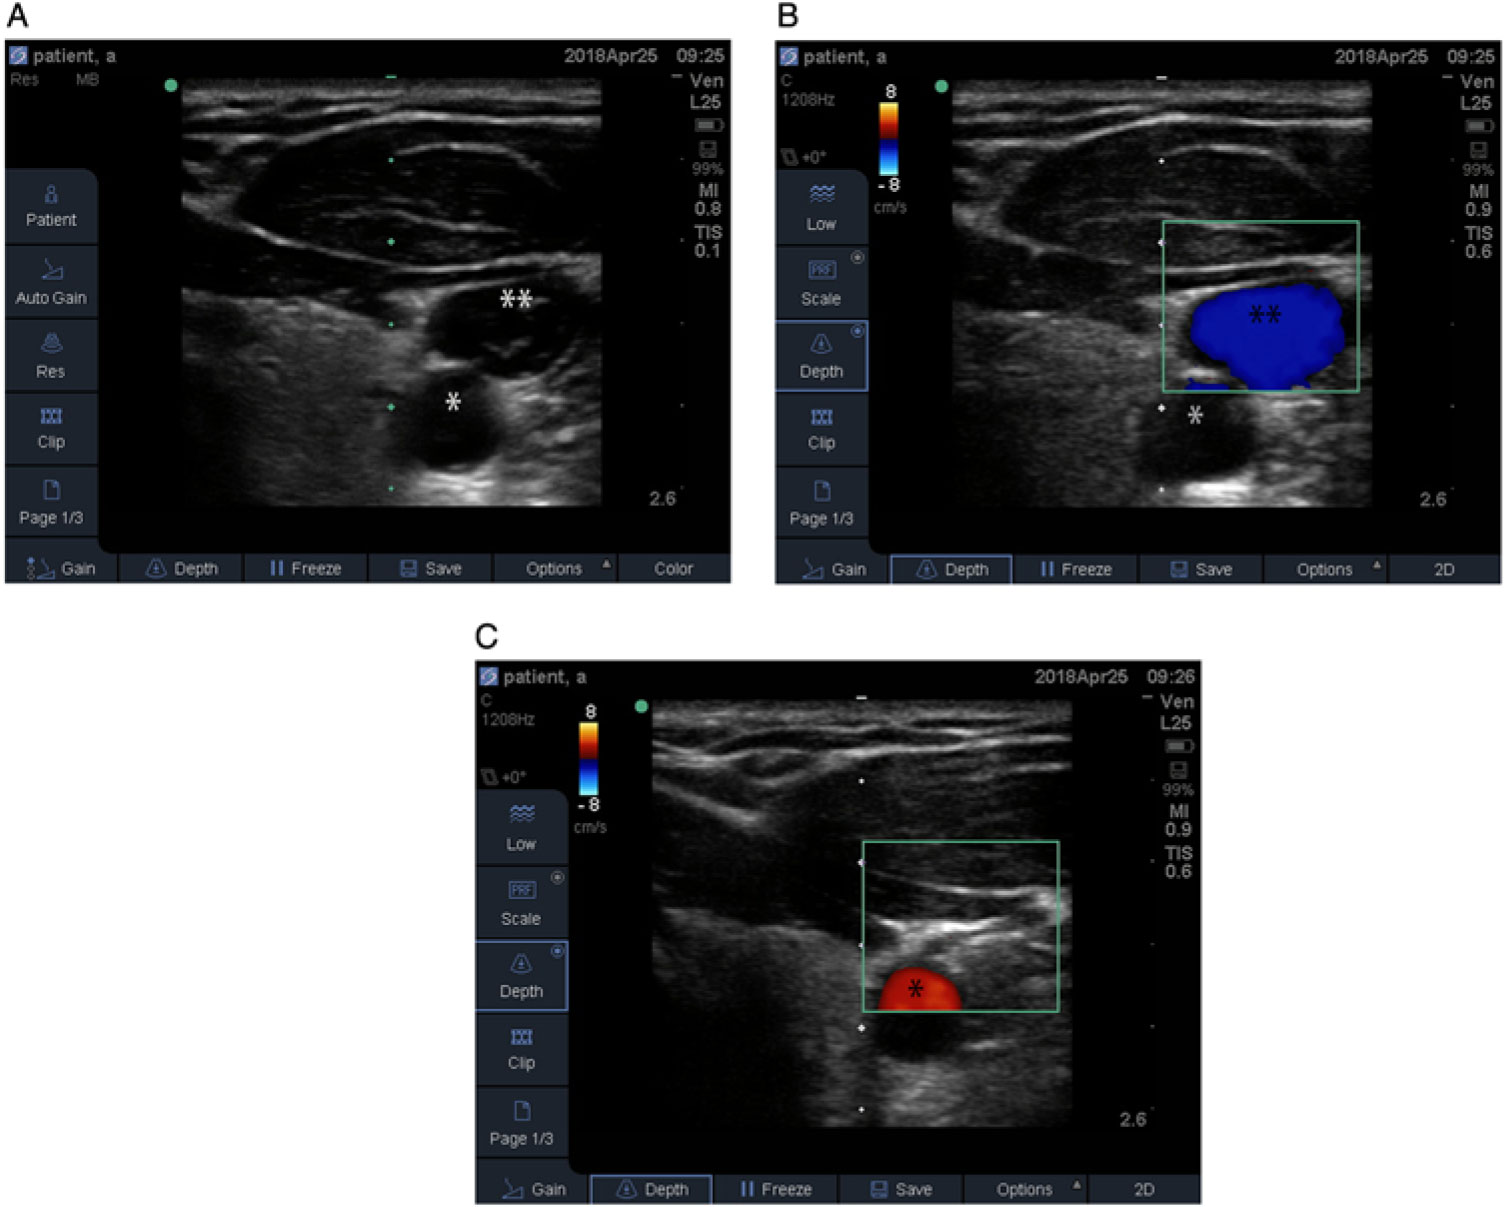

Figure 2: Ultrasound images of the left neck showing (A) without color Doppler, the common carotid artery (*) and IJ vein (**), (B) the common carotid artery (*) and IJ vein (**) with color Doppler, and (C) the common carotid artery (*) and compressed IJ vein at 53° of left neck rotation.